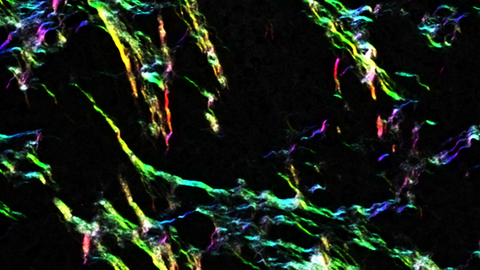

Collagen a key player in breast cancer metastasis

Researchers found that the levels of collagen XII in a tumour’s microenvironment alter tumour properties and make it more aggressive. In a study focused on breast cancer, researchers found that high levels of collagen XII were associated with increased metastasis and poorer survival rate. This research suggests that levels of collagen XII in tumour biopsies could potentially be used to identify patients with more aggressive types of breast cancer.